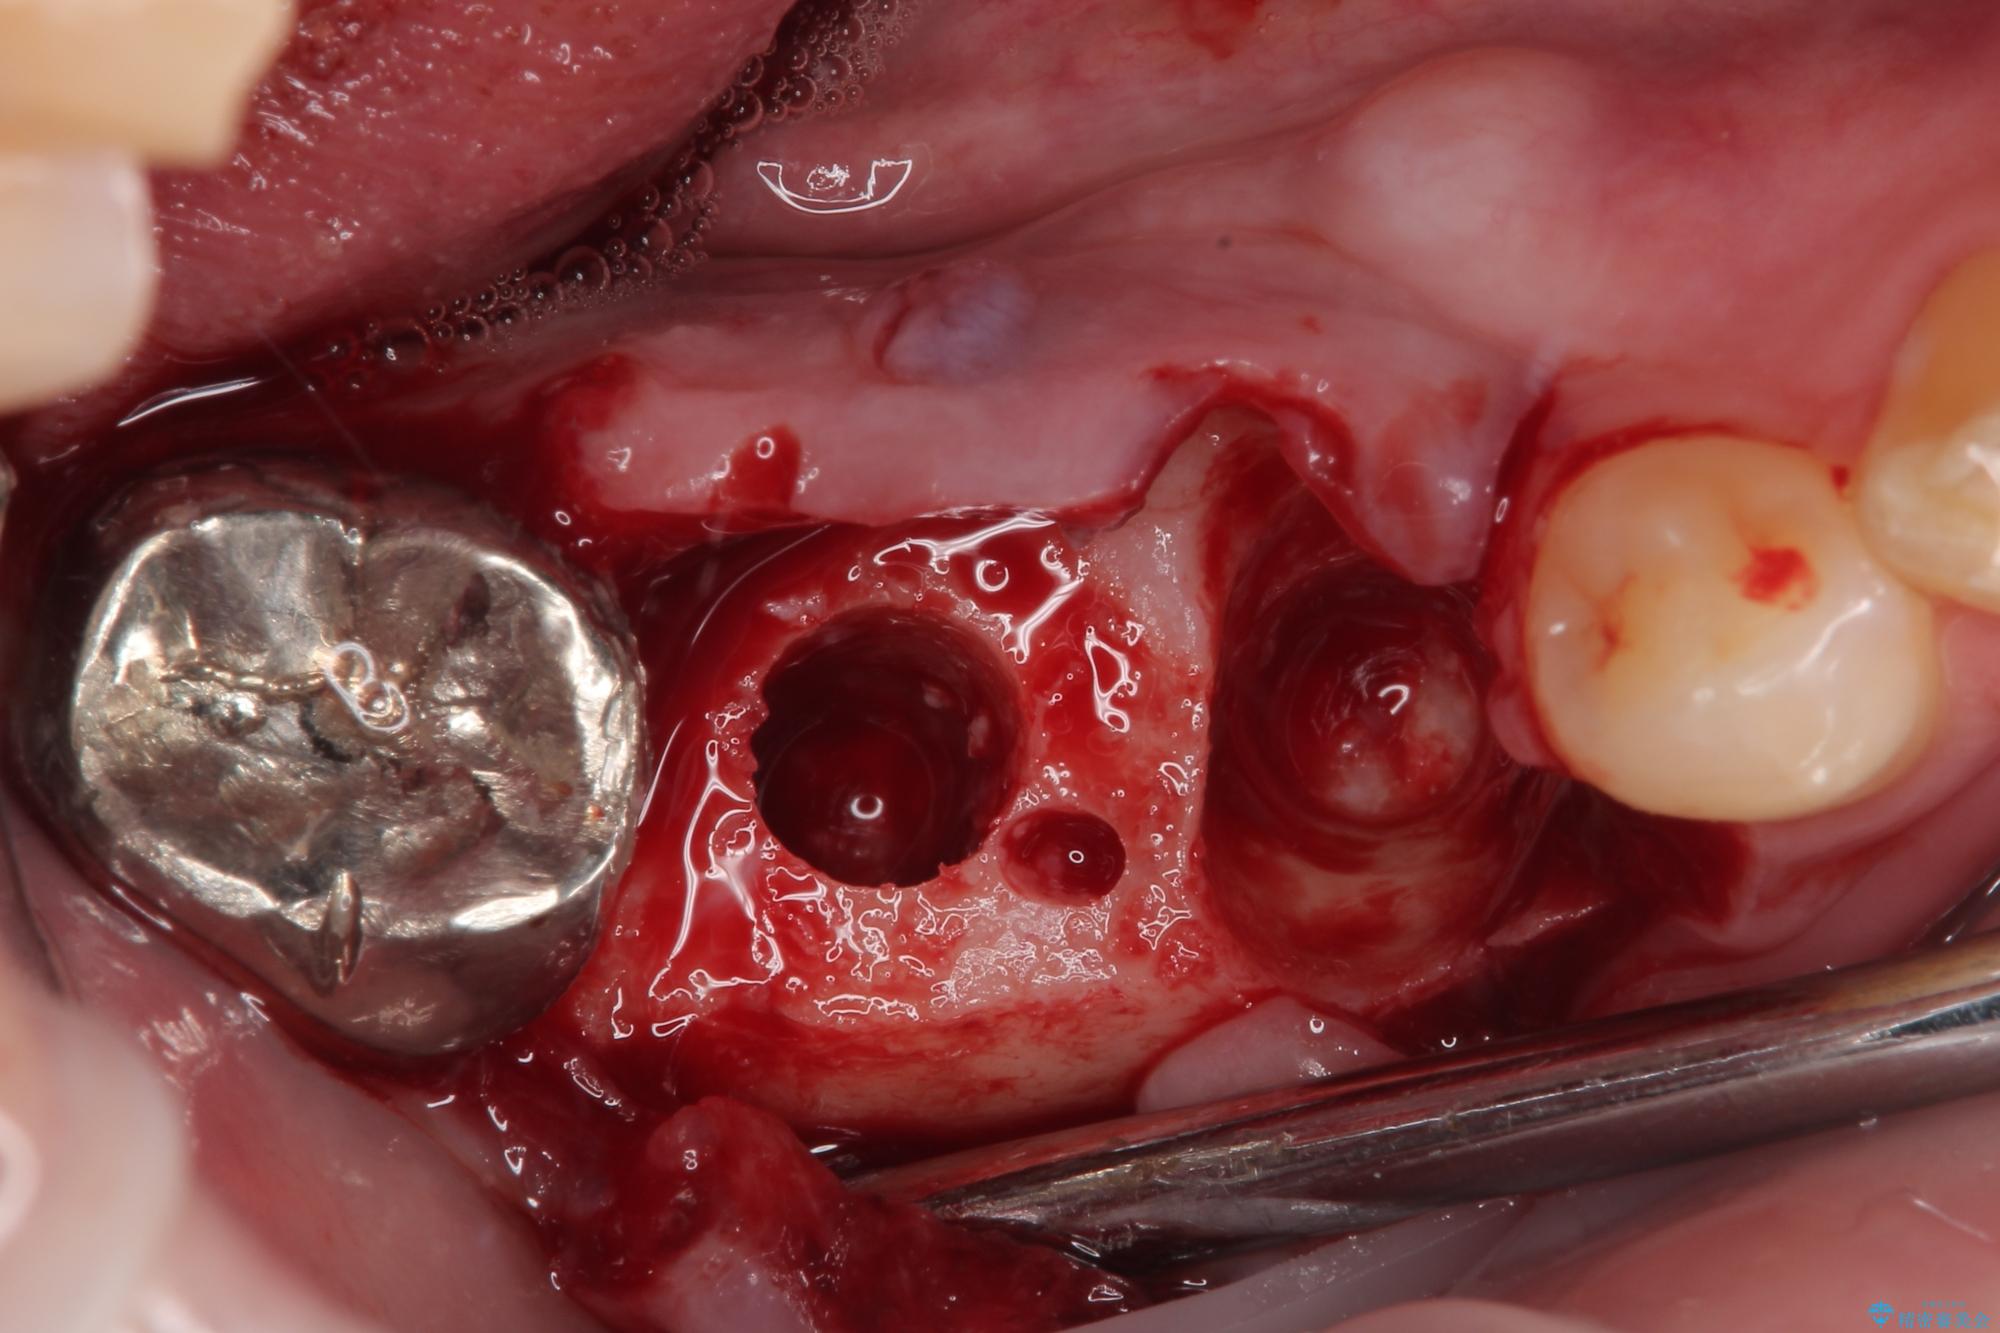

抜歯即時埋入部と後方の欠損部は、即日荷重(インプラント埋入と同時に仮歯を装着すること)が可能な安定値が得られましたが、長い期間欠損した状態で過ごすと、欠損部に舌を押し当てる癖が発現してしまい、舌からの側方圧でインプラントが脱離するリスクが著しく高まってしまうため、即日荷重は行いませんでした。